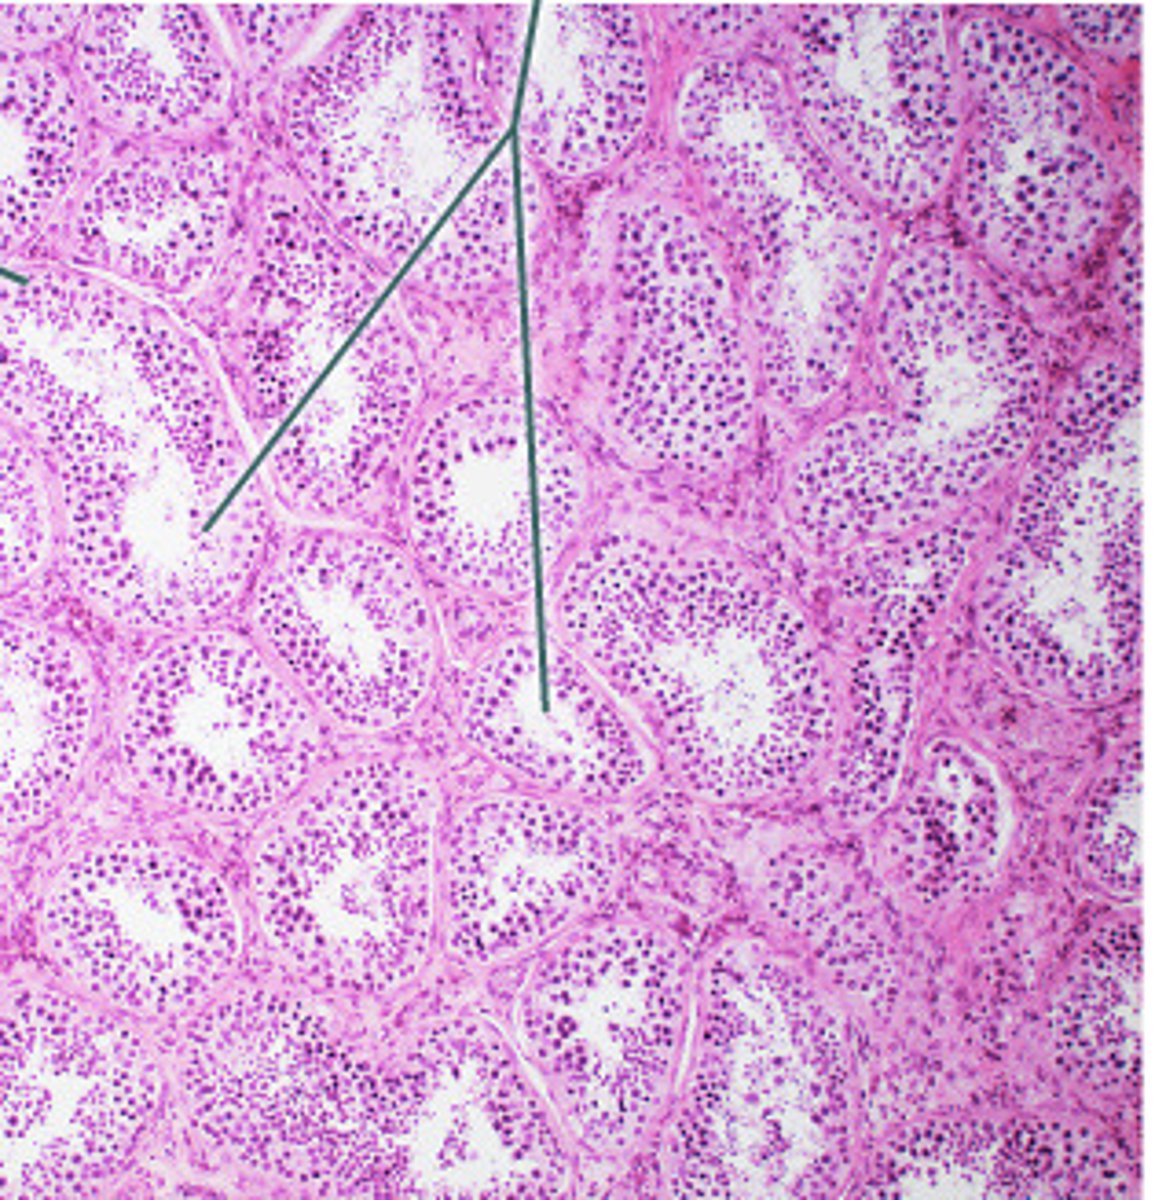

Testes: Testosterone, Inhibin

Both produced in Interstitial Cells of the testes

Name this gland and hormones produced (and location)

Seminiferous Tubules

Identify the structures